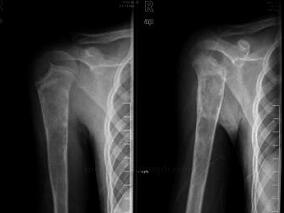

男14岁,右上臂隐痛2年,加重1周伴功能障碍1小时

1小时条评论患者,男性,14岁,2年前出现右上臂隐痛,呈间歇性。近2年身高增长明显,1周来疼痛加剧,于1小时前扭伤后出现功能障碍。 主诉 右上臂隐痛2年,加重1周伴功能障碍1小时 一、病史询问及思维提示 1. 病程与肿瘤性质的关系。 肿瘤的发展过程、进展速度和病程长短与肿...